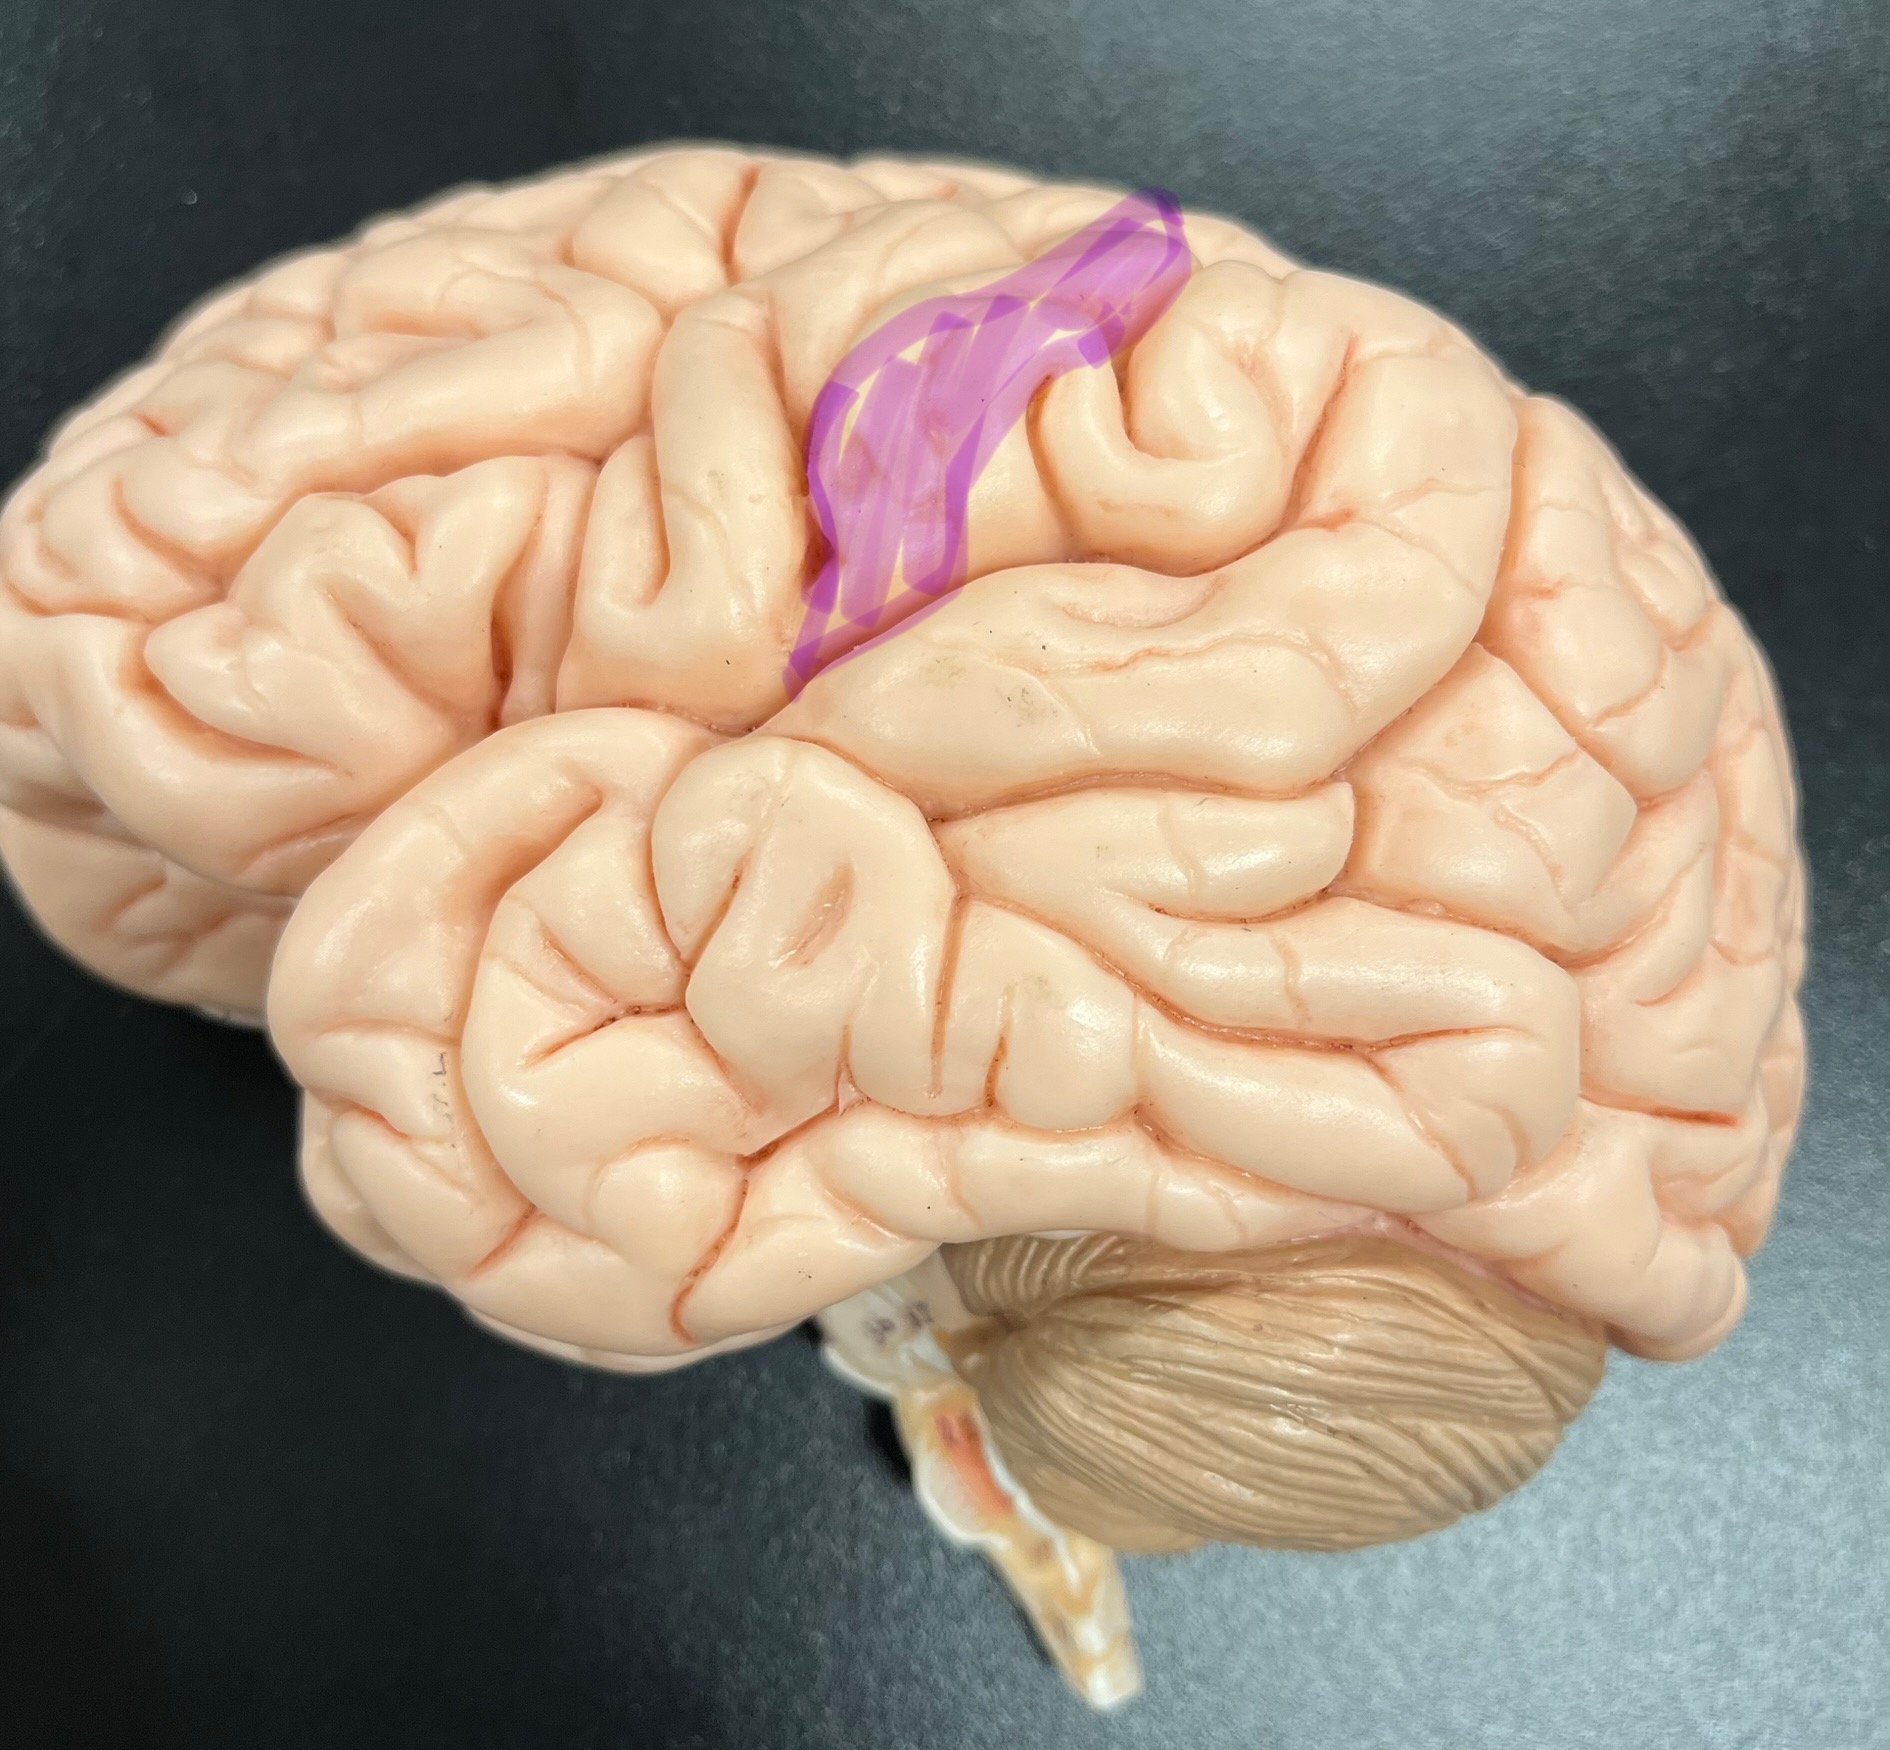

Divides parietal from frontal lobe

central sulcus

precentral gyrus

postcentral gyrus